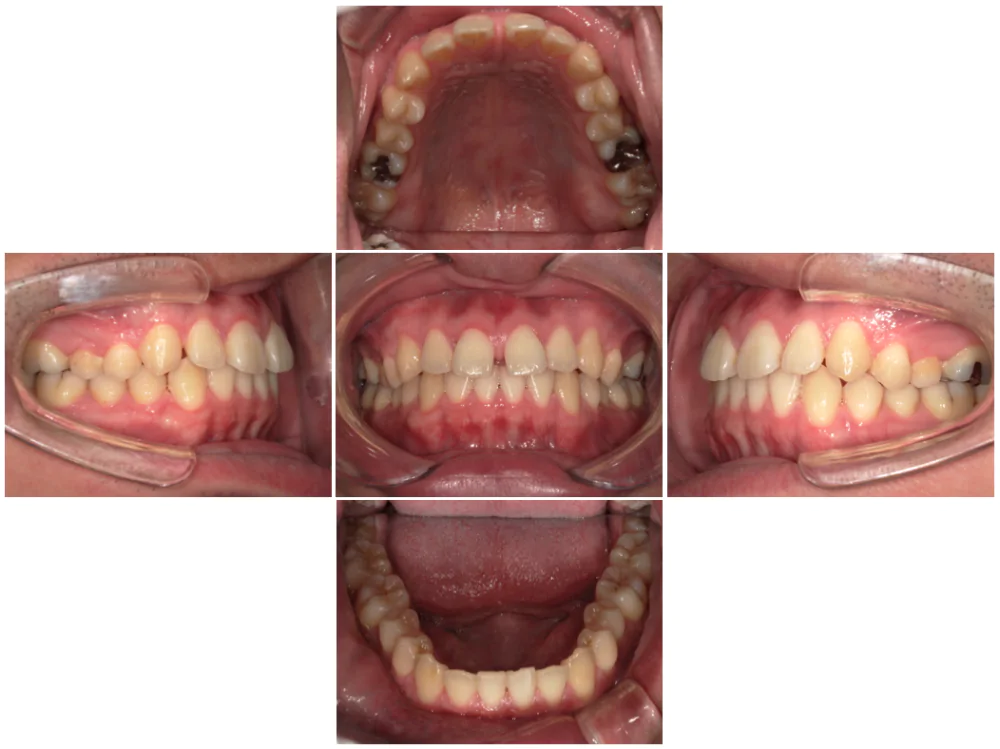

症例1

| 来院時の主訴 |

全体的なガタガタを治したい。

できれば抜歯はしたくない。

歯並びを気にせず笑えるようになりたい。

| 医院での対応や適用装置 | マウスピース矯正装置を使用して主訴であるガタガタを改善しました。 ガタガタの改善に必要なスペースの確保のために上あごの親知らずのみ抜歯を行いました。 |

| 通院期間 | 1年1ヶ月 |

| 通院回数 | 7回(治療中) |

| 治療費用総額 | 725,000円(税込) |

| リスクと副作用 | 矯正治療による歯の移動に伴う痛み、歯根吸収、虫歯 |